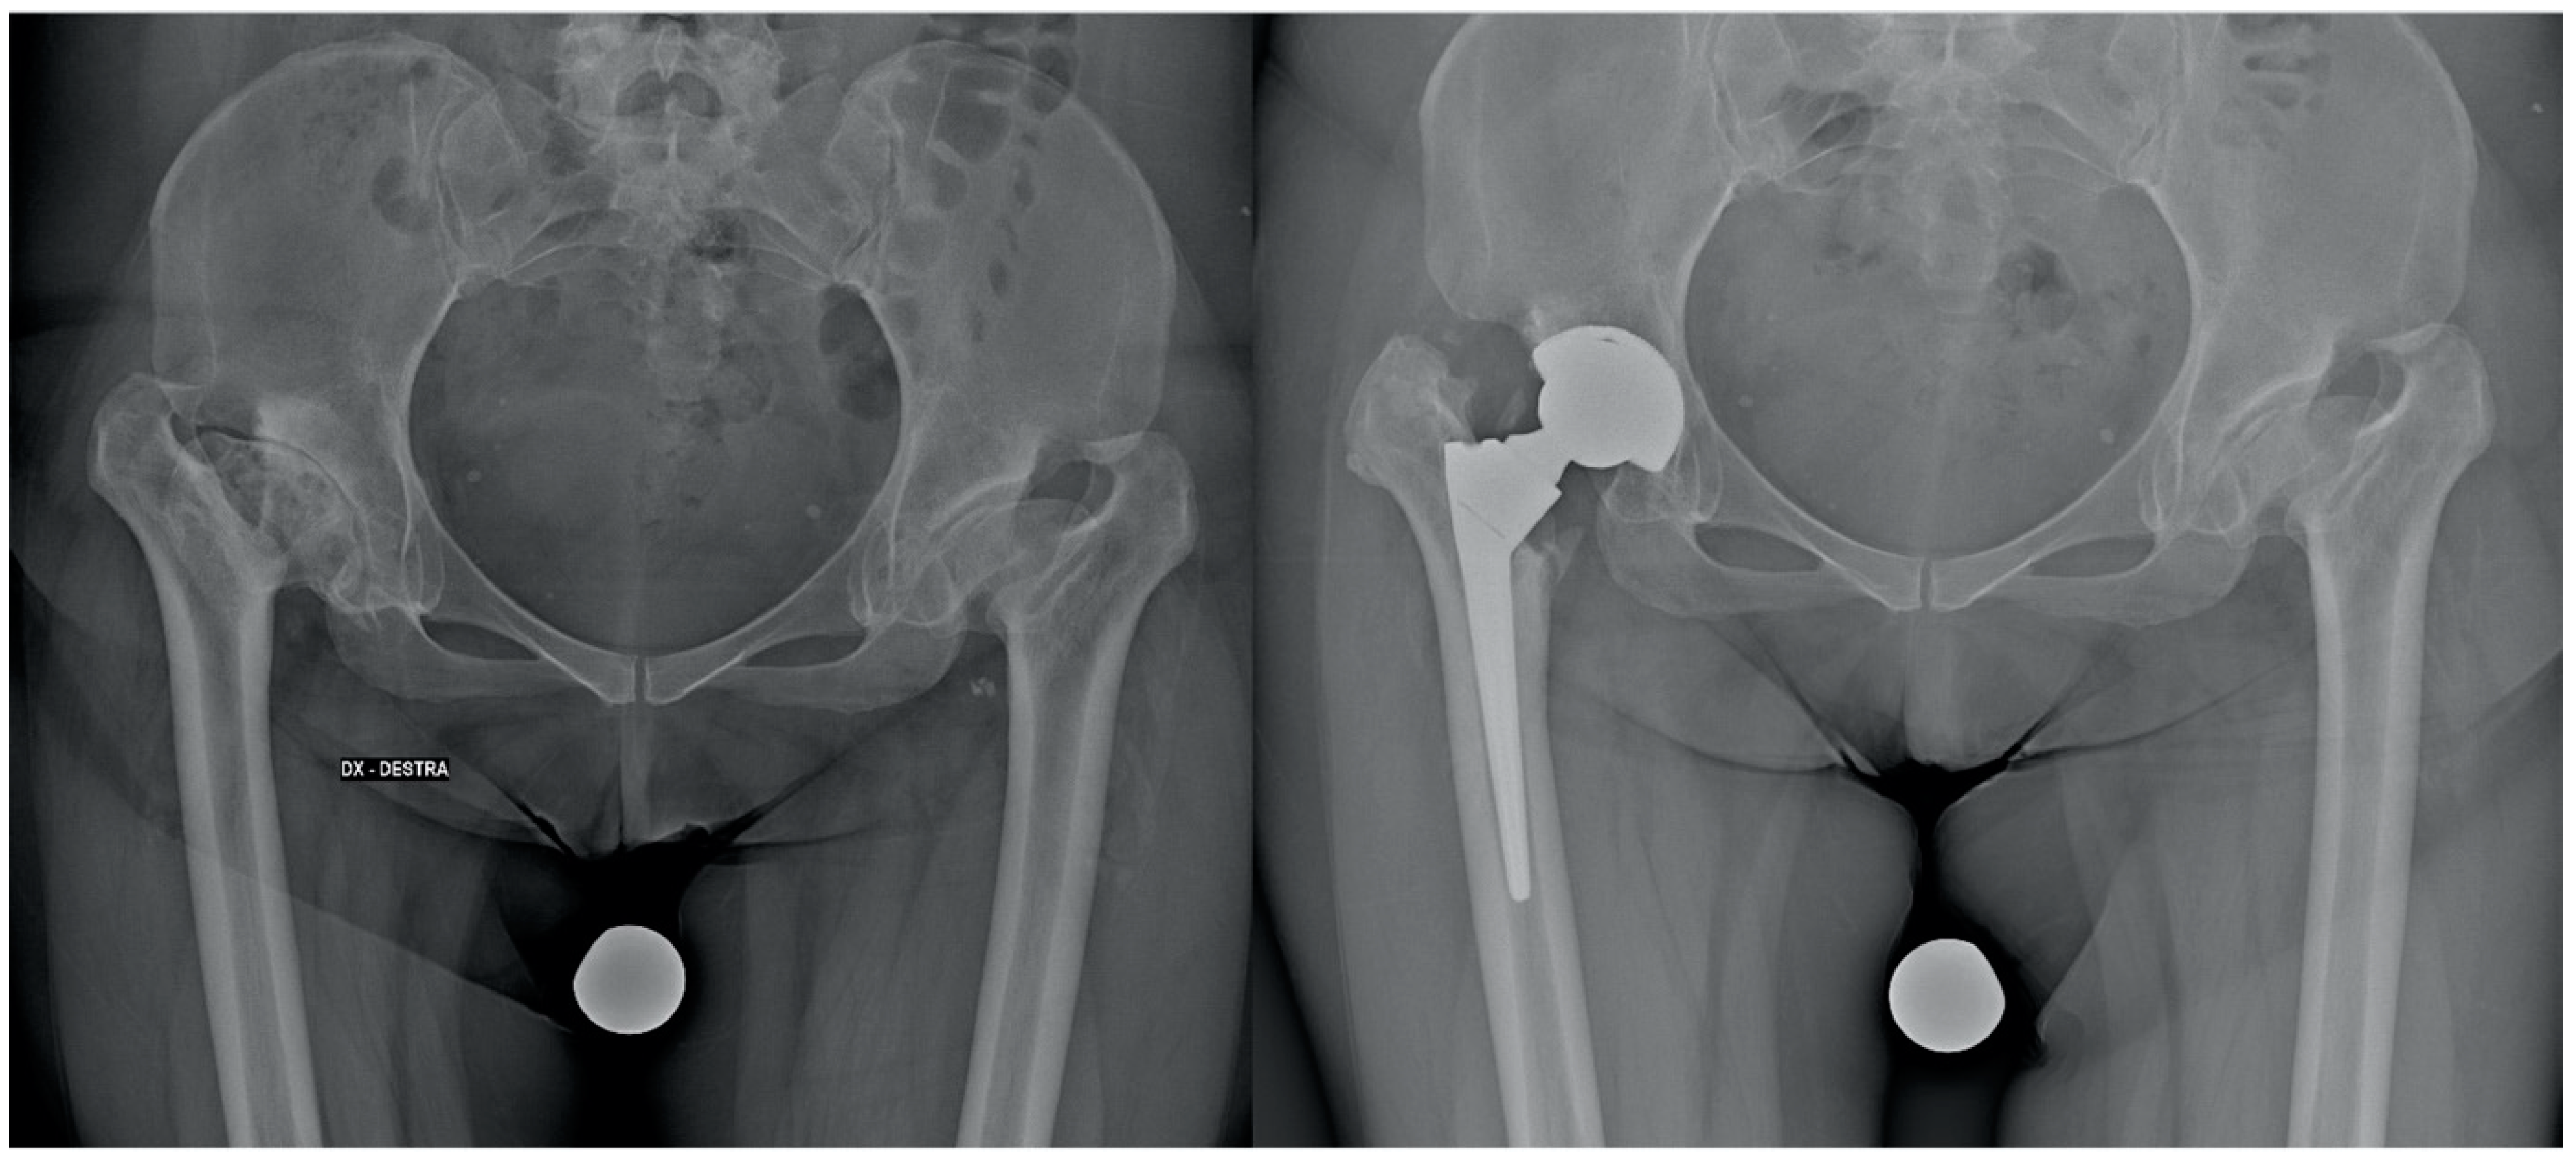

| Pre-operative Crowe classification | I: 26 (65%) II: 14 (35%) |

| Type of stem | Anatomical (Apta Adler Ortho): 16 (40%) Conical (ADR, Smith and Nephew; Wagner Cone, Zimmer; Alata Acuta, Adler): 24 (60%) |